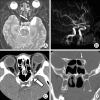

A 35-year-old man's vision had progressively deteriorated over a 3-month period. His left visual acuity was 5/20. Enhanced orbital computed tomographic (CT) scans revealed a fusiform dilatation of the ophthalmic artery in the left optic canal. Cerebral Angiography revealed a fusiform aneurysm on the left ophthalmic artery in the optic canal, measuring 6.2 x 4.6 mm in size. Four days after admission, visual acuity dropped to hand-motion. Endovascular treatment was chosen and a microcatheter was guided into the proximal segment of the ophthalmic artery. Using 4 detachable coils, parent artery occlusion was done. Three months after the intervention, the visual acuity in his left eye improved to 20/20. Dramatic recovery of visual acuity is exceptional with an ophthalmic artery trunk aneurysm. When an occlusion of the proximal ophthalmic artery is the only treatment option in such a situation, the endovascular occlusion of the proximal ophthalmic artery is quite feasible in the sense that it does not require any optic nerve manipulation.